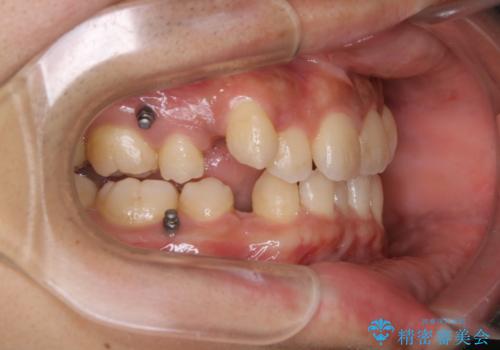

インビザライン単独でここまでできる!!抜歯矯正

- 治療計画

- マウスピースによる矯正治療をご希望された方です。歯のガタつきが大きかったため、ワイヤーによる抜歯矯正をご提案しました。どうしてもマウスピースが良いとの強いご希望があったため、治療の途中でワイヤー治療に切り替える可能性もあることを十分ご理解いただいた上でインビザラインによる抜歯矯正治療を行いました。

1日20時間以上、正しくインビザラインを使用して頂いたおかげで、ワイヤーに切り替えることなく矯正治療を終了することが出来ました。周囲からも歯並びがすごく綺麗になったと言われたのことで大変ご満足いただけました。